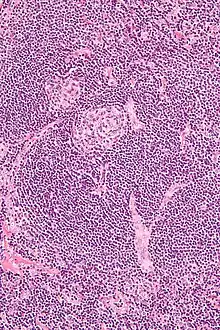

| Micrograph of Castleman disease showing hyaline vascular features including atrophic germinal center, expanded mantle zone, and a radially penetrating sclerotic blood vessel ("lollipop" sign). H&E stain. | |

- Hyaline vascular: regressed germinal centers, follicular dendritic cell prominence or dysplasia, hypervascularity in interfollicular regions, sclerotic vessels, prominent mantle zones with an "onion-skin" appearance.[14]

UCD most commonly demonstrates hyaline vascular features, but plasmacytic features or a mix of features may also be seen.[7] iMCD more commonly demonstrates plasmacytic features, but hypervascular features or a mix of features are also seen. All cases of HHV-8-associated MCD are thought to demonstrate plasmablastic features—similar to plasmacytic features, but with plasmablasts present.[13] The clinical utility of subtyping Castleman disease by histologic features is uncertain, as histologic subtypes do not consistently predict disease severity or treatment response.[13] Guidelines recommend against using histologic subtype to guide treatment decisions. Staining with latency-associated nuclear antigen (LANA-1), a marker for HHV-8 infection, should be measured in all forms of Castleman disease but is positive only in HHV-8-associated MCD.[15]